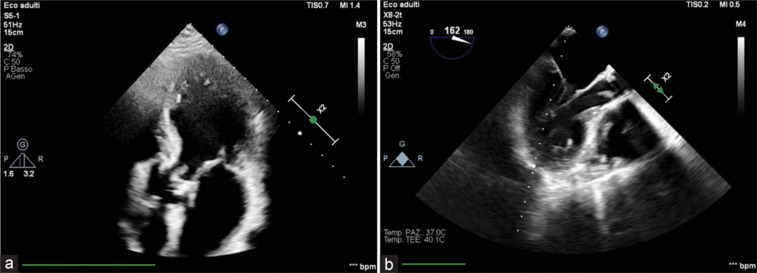

Infective endocarditis (IE) is a potentially life-threatening condition characterized by infection of the heart valves or endocardial surface, leading to significant morbidity and mortality. This case series explores four unusual presentations of IE, highlighting the diverse etiologies and complex multisystem complications that can arise from this condition. The clinical manifestations of IE can vary widely, ranging from systemic embolization to acute heart failure, reflecting the varied spectrum of pathogens involved and the patient's underlying health status. Key risk factors include preexisting valvular heart disease, intracardiac devices, intravenous drug use, and immunocompromised states. Prompt and accurate diagnosis is crucial for effective management, with echocardiography serving as the gold standard imaging modality and playing a key role as the first-line tool. Both transthoracic and transesophageal echocardiography are invaluable in identifying vegetations, evaluating valve function, and detecting potential complications such as abscesses, valve perforation, and intracardiac fistulas. The high sensitivity and specificity of echocardiography allow for early detection, even in cases with subtle or atypical presentations, ensuring that timely medical or surgical interventions are initiated. In addition, echocardiography is essential in monitoring treatment response, guiding clinical decisions, and determining the need for surgical valve replacement when severe damage or persistent infection is evident. This series emphasizes the importance of a multidisciplinary approach to treatment, which may include both medical and surgical interventions, tailored to the patient's specific clinical scenario. A heightened awareness of atypical presentations and the need for timely intervention are critical for improving patient outcomes, particularly in high-risk populations.